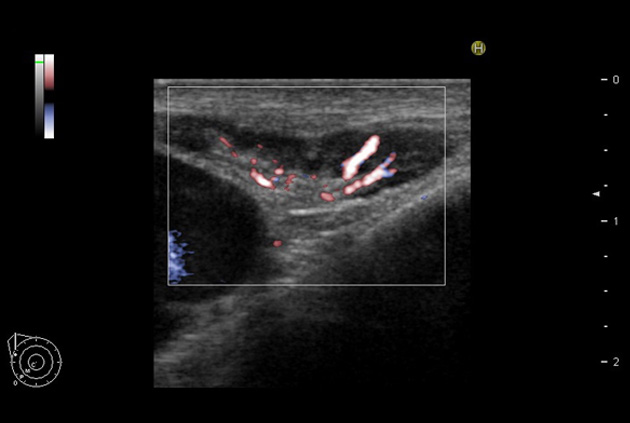

Giving the surgeon complete control

The Fujifilm Healthcare transducer utilizes the full benefits of the Wrist Articulation™ of the robotic instruments to capture real-time ultrasound imaging even at complex angles and difficult-to-reach areas.

Our smallest footprint allows for enhanced contact in tight spaces

Our newest probe, the L51K allows the surgeon access to difficult-to-reach areas that no other probe on the market can go. The unique design and proximal location of the attaching mechanism provides full wrist articulation and easier grasp and release.

The next level in Robotic Ultrasound

Full wrist articulation with optimized functional length.

A critical function of robotic ultrasound guidance is tumor margin identification. Fujifilm's family of robotic probes all have the optimum location of the attaching mechanism that allows for full wrist articulation of the probe. The result is an increased confidence that the tumor margins have been completely identified.